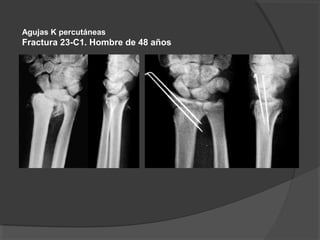

Agujas K percutáneas

Fractura 23-C1. Hombre de 48 años